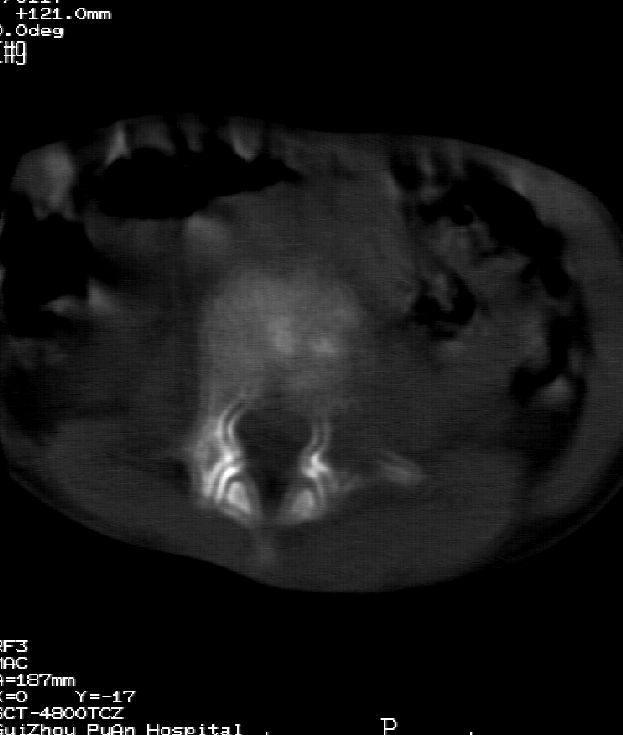

乍一看像是嗜酸性肉芽肿,但看到ct表现骨质破坏及软组织肿胀考虑结核可能性大,鉴别恶性肿瘤.

本例ct图像太不清楚了,而且不知道有没有传完,如果软组织病变只局限性于那几个层面的话多考虑嗜酸性肉芽肿,其次为其他肿瘤,结核椎旁软组织较广泛,在本例没有太典型表现,建议楼主(孩子父母吧)把所有的软组织窗图像(白色的那种)按顺序全部转上来.

考虑l3嗜酸性肉芽肿。